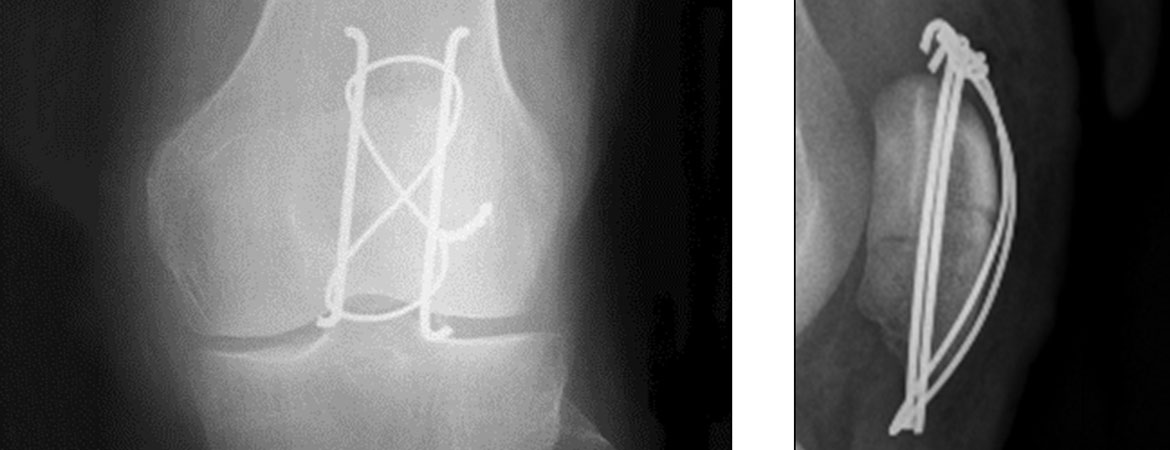

Sylvain Steinmetz, Alexandre Brügger, Jules Chauveau, François Chevalley, Olivier Borens, Eric Thein (Author) Practical guidelines for the treatment of patellar fractures in adults Fulltext PDF Fulltext HTML